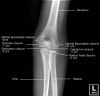

6. Forearm AP view

7. Forearm Lateral view(bent/straight arm)